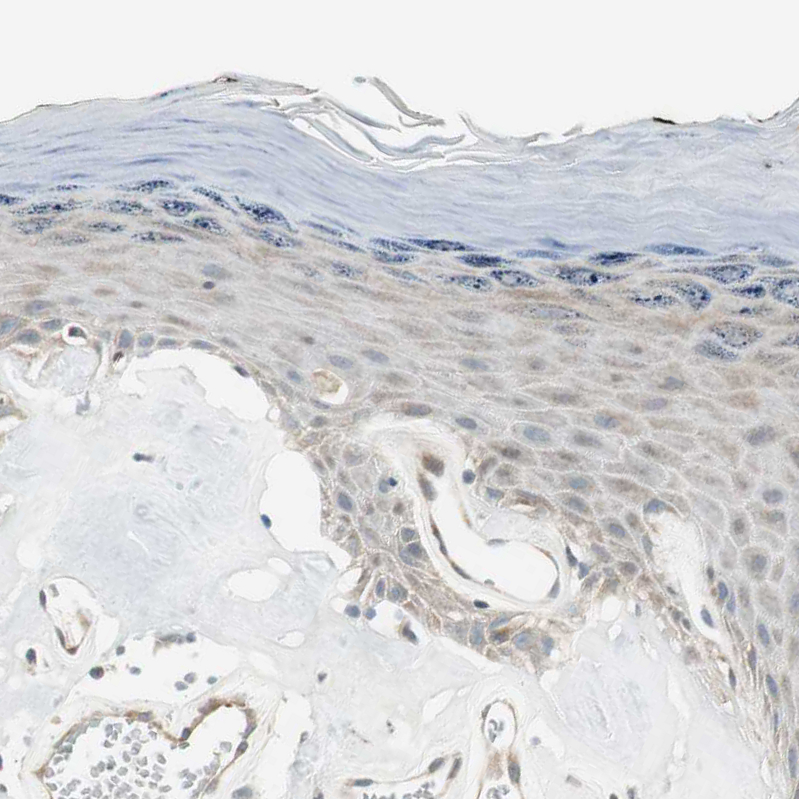

Immunohistochemical staining of human testis shows strong nuclear and cytoplasmic positivity in cells in seminiferous ducts.